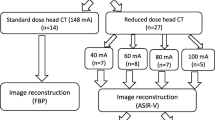

In CT, ionizing radiation exposure from the scan has attracted much concern from patients and doctors. This work is aimed at improving head CT images from low-dose scans by using a fast Dictionary learning (DL) based post-processing. Both Low-dose CT (LDCT) and Standard-dose CT (SDCT) nonenhanced head images were acquired in head examination from a multi-detector row Siemens Somatom Sensation 16 CT scanner. One hundred patients were involved in the experiments. Two groups of LDCT images were acquired with 50 % (LDCT50 %) and 25 % (LDCT25 %) tube current setting in SDCT. To give quantitative evaluation, Signal to noise ratio (SNR) and Contrast to noise ratio (CNR) were computed from the Hounsfield unit (HU) measurements of GM, WM and CSF tissues. A blinded qualitative analysis was also performed to assess the processed LDCT datasets. Fifty and seventy five percent dose reductions are obtained for the two LDCT groups (LDCT50 %, 1.15 ± 0.1 mSv; LDCT25 %, 0.58 ± 0.1 mSv; SDCT, 2.32 ± 0.1 mSv; P < 0.001). Significant SNR increase over the original LDCT images is observed in the processed LDCT images for all the GM, WM and CSF tissues. Significant GM–WM CNR enhancement is noted in the DL processed LDCT images. Higher SNR and CNR than the reference SDCT images can even be achieved in the processed LDCT50 % and LDCT25 % images. Blinded qualitative review validates the perceptual improvements brought by the proposed approach. Compared to the original LDCT images, the application of DL processing in head CT is associated with a significant improvement of image quality.